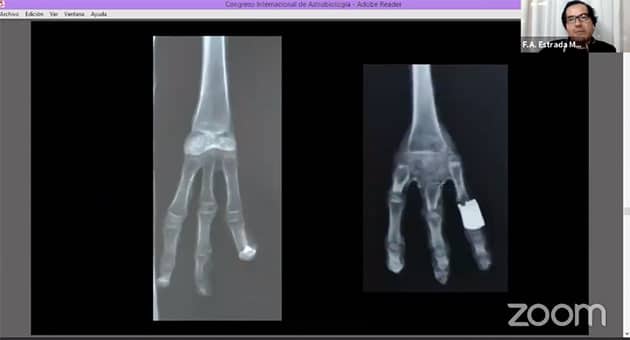

„Probe 06“ soll offenbar als große, erneut dreifingerige Hand erscheinen und hat eine Länge von knapp 30 Zentimetern. Hier ziert eine sichel-/halbreisförmige Metallplatte den Handrücken.

Auch hier zeigt die Röntgenaufnahme (Abb. 32) zum einen den „Metallschmuck“ und zum anderen, dass der Handteller und die Handwurzeln aus (menschlichen) Fingergliedern zusammengepackt wurden. Die echten Handtellerknochen wurden freigelegt, um so die Hand bzw. die Finger größer erscheinen zu lassen. Selbiges gilt für die Finger. Diese wurden durch weitere Fingerknochen verlängert, dies aber teils anatomisch völlig falsch – einige Fingerknochen wurden hier sogar falsch herum angesetzt. Die gesamte Hand (inklusive der zusätzlichen Fingerknochen) ist menschlich.

Auch die untersuchten „Proben 07 und 08″ (Abb. 33, 34) zeigen jeweils einzelne Hände, die nach dem gleichen Muster wie „Probe 06“ (Abb. 31, 32) hergestellt wurden.